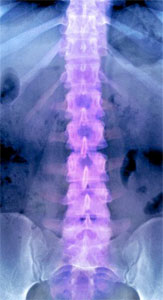

Chiropractors are the spinal health experts. Helping to restore proper spinal biomechanics and improved nervous system function begins with a patient’s case history. This gives the chiropractor a background about your health, such as surgeries, accidents, the onset of your condition, and other details affecting your current health. After reviewing your history and discussing your specific problem, a thorough orthopaedic, neurological, and chiropractic examination is performed. X-rays may be taken to uncover structural and functioning problems associated with the spinal column. These examinations help identify areas of spinal malfunction and resulting nervous system deficit. The findings of these examinations are explained and a plan of chiropractic adjustments may be recommended. Progress is monitored with periodical examinations and follow-up reports.